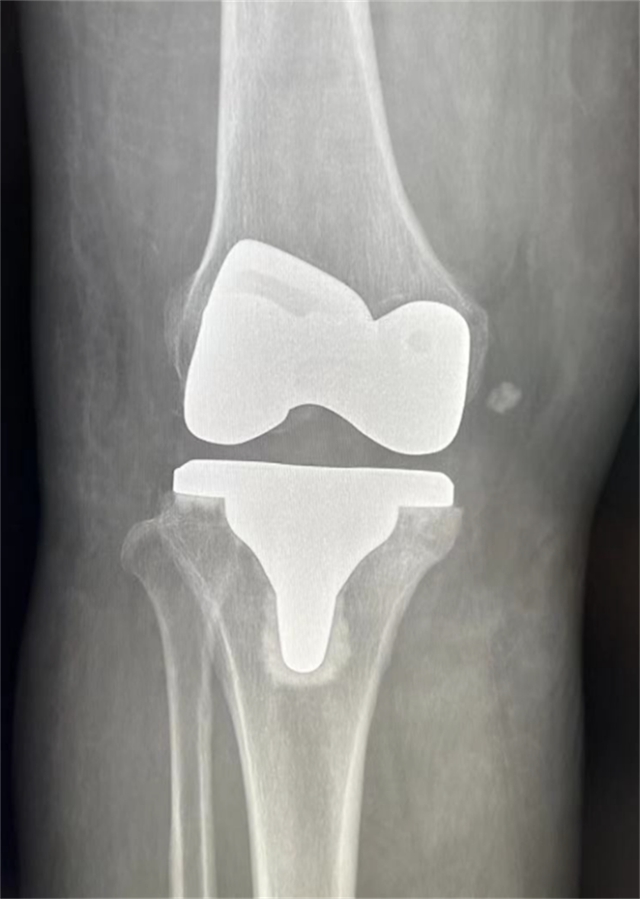

患者术后影像资料